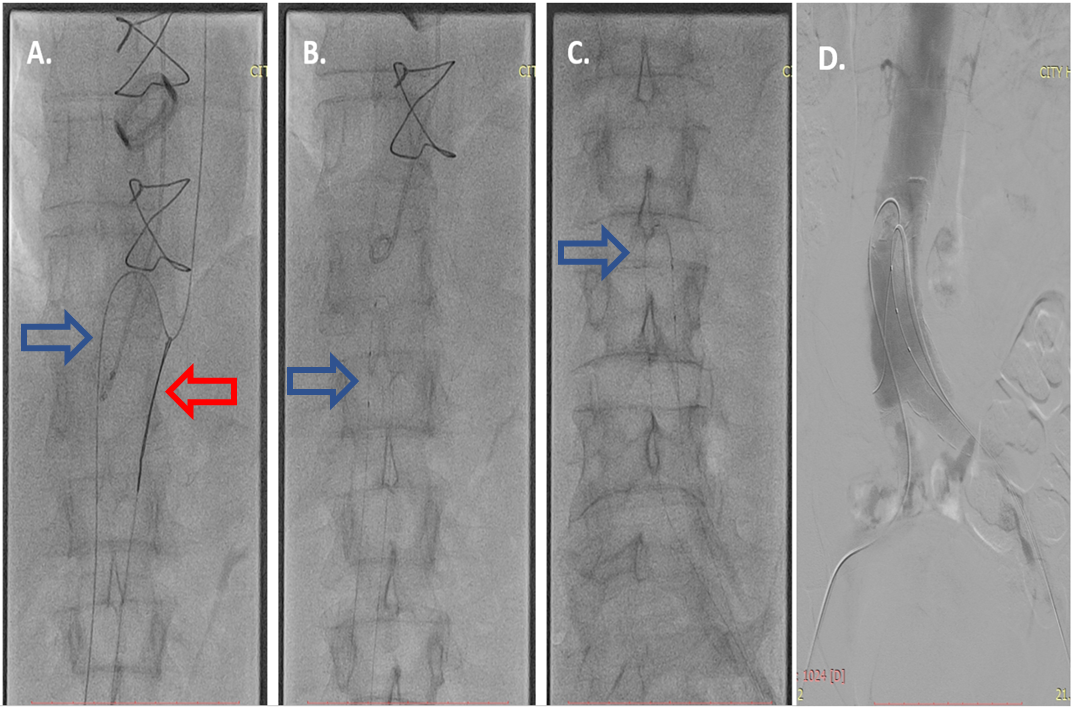

Fig. 2.Fenestration of the intima. (A) The hydrophilic Whisper Extra Support guidewire 0.014” (Abbot) in the true lumen (blue arrow) was caught with a lasso (Amplatz Goose Neck, EV3) (red arrow) and was passed from the true to the false lumen. (B) Fenestration of the proximal part of the intima with the help of microcatheters in the true and false lumen (blue arrow). (C) Fenestration of the distal part of the intima (blue arrow) indicating the microcatheters. (D) Showing the successfully created single lumen of the abdominal aorta.